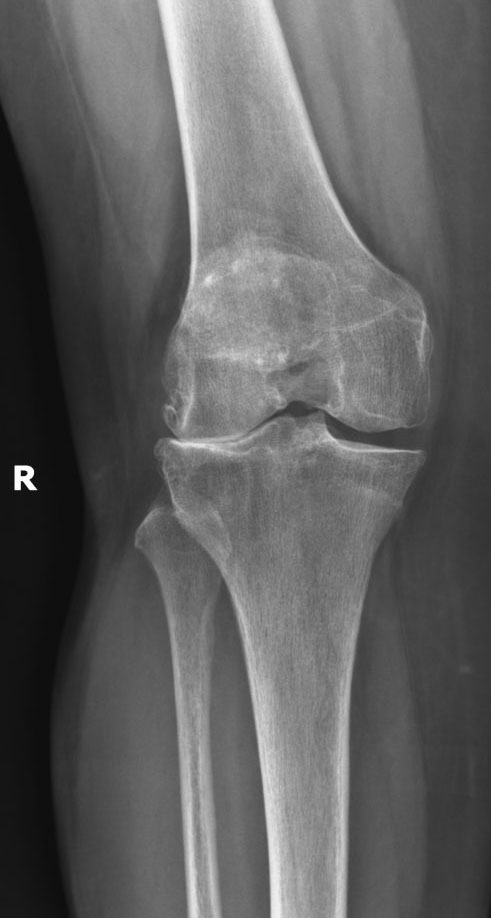

Several years ago I was diagnosed with a meniscus tear in my knee. I have a high-powered demanding job and decided not to do anything about my knee on the advice of a doctor. My knee kept getting worse until it was time to see another doctor. I tried various treatments, all of them failing miserably. My rheumatologist at HSS told me based on my x-rays I needed knee surgery. Because of my hectic work schedule I opted to wait a few months, until suddenly my other knee started hurting with a vengeance. This time there was no waiting. I had no quality of life and lived with unbearable pain. I knew I couldn’t wait any longer and made an appointment to see a surgeon at HSS. Upon meeting him, I observed a friendly, compassionate and caring man. Both knees needed total replacement and we discussed which knee should be replaced first. With the help of my surgeon's incredibly and caring staff, my surgery was scheduled. I was terrified of having surgery. Everyone warned me how terrible the surgery was but I didn’t have a choice. The surgery was no picnic but honestly, it wasn’t terrible either. Two weeks after my surgery I was walking without a cane, and more importantly, no pain. There are no words to thank my surgeon. He gave me my life back and I will be forever grateful. I will soon be replacing my other knee and look forward to returning to all the activities I was unable to do for years. My advice to anyone who is putting off total knee replacement due to fear, no need to be afraid. HSS will give you your life back!